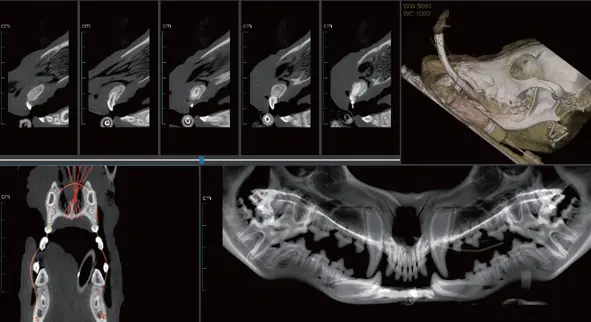

PANAROMİK

Tam Ark ve Çene için Tek Tarama

Yüksek çözünürlüklü dental görüntüler sunar; akıllı artefakt düzeltme sayesinde pulpa boşluğu ve periodontal ligament gibi ince yapılar net bir şekilde görüntülenir.